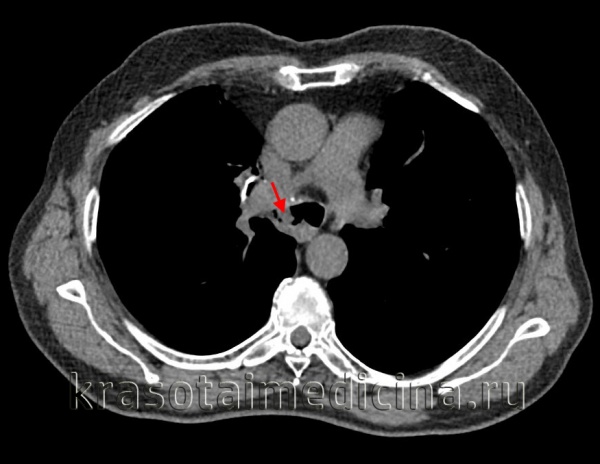

![КТ органов грудной клетки. Стеноз правого главного бронха за счет мягкотканного образования в его просвете.]()

КТ органов грудной клетки. Стеноз правого главного бронха за счет мягкотканного образования в его просвете.